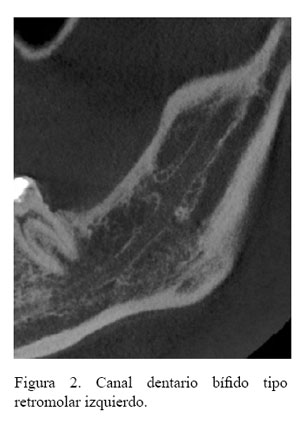

Tipo 1 (Canal retromolar): Consiste en una bifurcación del canal mandibular en la región de la rama mandibular, no alcanza piezas dentales, el conducto realiza una curva y alcanza la región retromolar (Figura 1 (A)).

En la tabla 3 se describe la distribución de la frecuencia del tipo de BCDI donde se encontraron 103 casos del tipo canal retromolar (Figura 2, figura 3 y figura 4); no se encontró ningún caso con el tipo de bifurcación canal bucal-lingual.